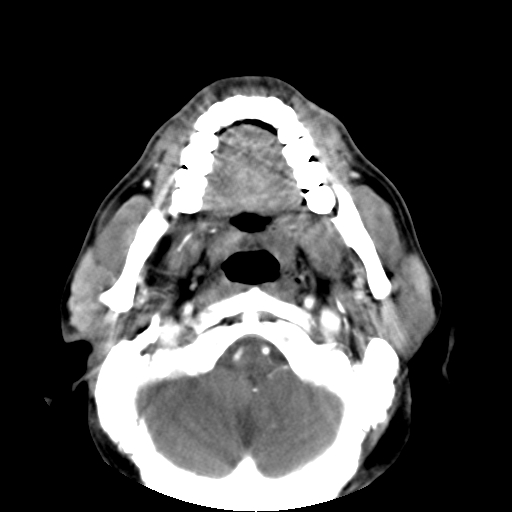

标题: CT24019:男,45岁,发现颈部肿物5个月。 [打印本页]

男,45岁,发现颈部肿物5个月,彩超示:双侧颈部及下颌部软组织增厚。

考虑双侧颈项部良性对称性脂肪增多症。